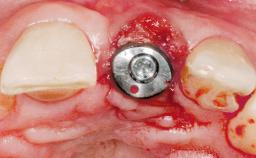

Immediate Flapless Placement of an Implant in a Maxillary Left Central Incisor Site

A 42-year-old female patient was referred to our clinic at the School of Dentistry of the University of São Paulo in November 2004, presenting a deficient restoration in the upper left central incisor. The clinical examination revealed no gingival retraction or any signs of gingival inflammation and, therefore, previous periodontal treatment was not considered. The patient presented a high lip line at full smile and a thin tissue biotype. This combination characterized a high-risk situation from an anatomic point of view, which required careful preoperative planning and cautious surgical execution.

Type of Implants One-Piece

Placement Protocol Immediate implant placement